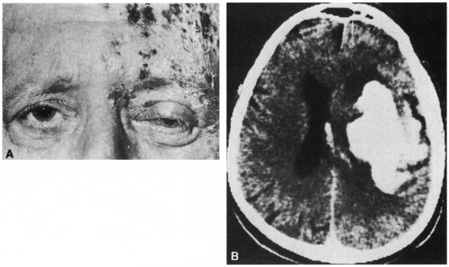

Herpes zoster ophthalmicus behaves like zoster infections elsewhere in the body. The incidence increases with age. Pain, often severe, may precede, be concurrent with, or follow the vesicular skin eruption. Occasionally no skin lesions occur; this is referred to as zoster sine herpete. The vesicular eruption usually involves only one dermatome, but severe systemic eruptions can occur (the latter appear most often in immunocompromised persons or in persons with malignancy). Fever, malaise, headache, and lymphadenopathy may be present at the onset. Fifty percent of cases have ocular involvement, which can be predicted if vesicles appear on the lid margin or if Hutchinson's sign is present.39,40 In 1886, Hutchinson noted that when the nasociliary branch to the tip of the nose is affected, intraocular involvement is likely. Ocular changes include conjunctivitis, episcleritis, scleritis, keratitis, iritis, chorioretinitis, optic neuropathy, glaucoma, ocular motor palsies, and Horner's syndrome.39,41,42 On rare occasions, a contralateral hemiplegia may occur (Fig. 7).39,43–45 A virus-induced angiitis of cerebral vessels has been shown by angiography and pathology in several cases. Although patients with neoplastic or other debilitating diseases are predisposed to the development of herpes zoster infections, a neoplasm is discovered in less than 1% of otherwise healthy persons with cutaneous zoster.

Fig. 7. A: A 70-year-old man with herpes zoster ophthalmicus and a left-cerebral infarction. B: Computed tomography demonstrates a hemorrhagic infarction.

Starting treatment for herpes zoster ophthalmicus should be accomplished as early as possible and ideally within 72 hours. Current recommendations to reduce the incidence of keratitis and possibly postherpetic neuralgia are to use an antiviral drug for 7 to 14 days, lubricating ointment until the cornea is completely healed, but no topical steroids.46 In immunocompetent people, any of the oral antivirals can be used: acyclovir, 800 mg orally five times per day; famciclovir, 500 mg orally three times daily; valacyclovir, 1,000 mg orally three times daily.47–49 Immunocompromised persons should receive intravenous acyclovir.